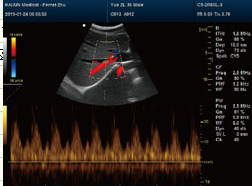

经外周中心静脉导管置管于20世纪80年代应用于临床,90年代后期在我国开始使用,现在很大程度上已被广大医护人员和患者认可,其极细的高生物相容性导管由肘前静脉穿刺插入至上腔···...